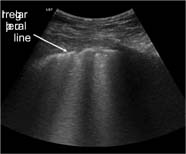

Pleural line (Figure 3): in a normal lung, only the pleural line can be seen. This appears as a hyperechoic and sliding line, moving forward and backward with ventilation. This is the result of the movement of the visceral pleura against the parietal pleura during the respiratory cycle.

FIG 3. Normal pleural line.